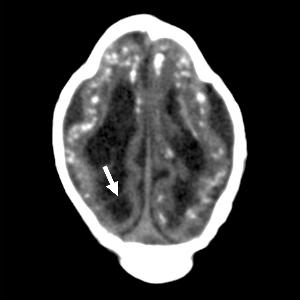

Intracranial calcifications were present in almost all of the neonates, most commonly found at the gray-white junction of the brain. All of the babies exhibited reduced tissue volume in their brains. All patients showed varying abnormalities in cortical development.

"The severity of the cortical malformation and associated tissue changes, and the localization of the calcifications at the grey-white matter junction were the most surprising findings in our research," Dr. Tovar-Moll said.

Figure 2. (a) Axial, (b) sagittal, and (c) coronal fetal T2-weighted MR images were obtained in a 29-year-old woman with confirmed Zika virus infection, initially seen for characteristic rash at 12 weeks of gestational age. (d) Axial postnatal CT image and (e–g) axial and (h) coronal T2-weighted MR images were obtained in her male neonate. The fetal MR images obtained at 34 weeks (a–c) show asymmetrical ventriculomegaly with a septation in the right occipital horn (arrowhead on a), small frontal lobes, thinning of the occipital parenchyma (left worse than right), underdeveloped sylvian fissures, and regions of thickened cortex, as in the right frontal lobe, which is suggestive of polymicrogyria (arrow on a). There is abnormal, increased signal intensity in the white matter. The postnatal CT image (d) obtained in the 22-day-old neonate shows punctate calcifications at the gray matter–white matter junction and asymmetrical ventriculomegaly. The T2-weighted MR images obtained at 26 days (e–h) show septation in the ventricle (arrowhead on e). Note how the right ventricle has relatively decreased in size compared with the prenatal image, whereas the left ventricle has increased in size. Under-rotation of the hippocampus (arrowheads on f) is demonstrated. There is clear asymmetry of the gyral pattern on g, which is relatively smooth in the left occipital region, with abnormal folds in the right occipital and frontoparietal regions (arrows on g). Subependymal cysts are visualized on h, which are not seen on fetal MR images.

Figure 4. Images obtained in the case of an 18-year-old woman, first seen for rash at 10 weeks of pregnancy, with confirmed Zika virus infection. US findings obtained at 20 weeks of gestational age were reportedly normal, with normal head circumference of 17.5 cm. At 37 weeks of gestational age, (a) sagittal transvaginal and (b) coronal transabdominal US images obtained with the head upside down show a small head circumference (26.4 cm, corresponding to 28 weeks 5 days, below the 3rd percentile), moderate ventriculomegaly with dense intracranial calcifications (arrowheads on a), and abnormal head shape with flattened appearance and thickened skin (arrow on a). On the sonogram, it is difficult to precisely localize the calcifications, given the thin parenchyma. (c, d) Axial bone window CT images, (e) sagittal localizer CT image, and (f–h) axial CT images show microcephaly with cerebral atrophy, and, despite ventriculomegaly, the extra-axial cerebrospinal fluid spaces are still prominent. The hypoattenuating calcifications are predominantly located in the subcortical white matter at the gray matter–white matter interface. There is markedly abnormal skull shape with some eversion of the bones at the suture sites (particularly frontoparietal sites), with redundant skin folds (particularly in the parieto-occipital region). (i) Sagittal T1-weighted, (j, k) coronal T2-weighted, and (l) axial susceptibility-weighted MR images obtained at 1 month of age show an undersegmented midbrain, severe microcephaly, open sylvian fissures, and polymicrogyria. The dense calcifications are evident on the susceptibility-weighted image. On the sagittal images (a, e, i), note the small supratentorial compartment and associated skull deformity.